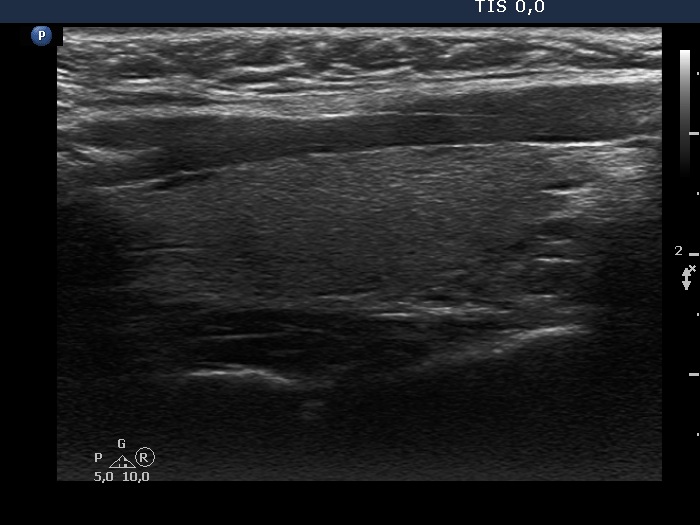

Study on 100 consecutive patients with thyroid nodule - case 051 (ultrasonographic picture 7)

Left lobe, longitudinal view.